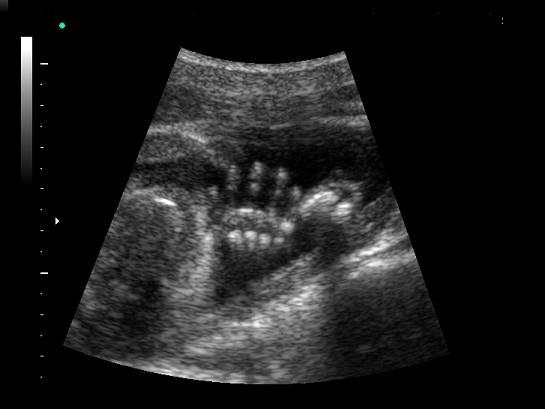

问题 如图,超声显示的是胎儿的哪一部位 ( )

选项 A、腹部 B、颈部 C、脚 D、腿 E、手

答案 E